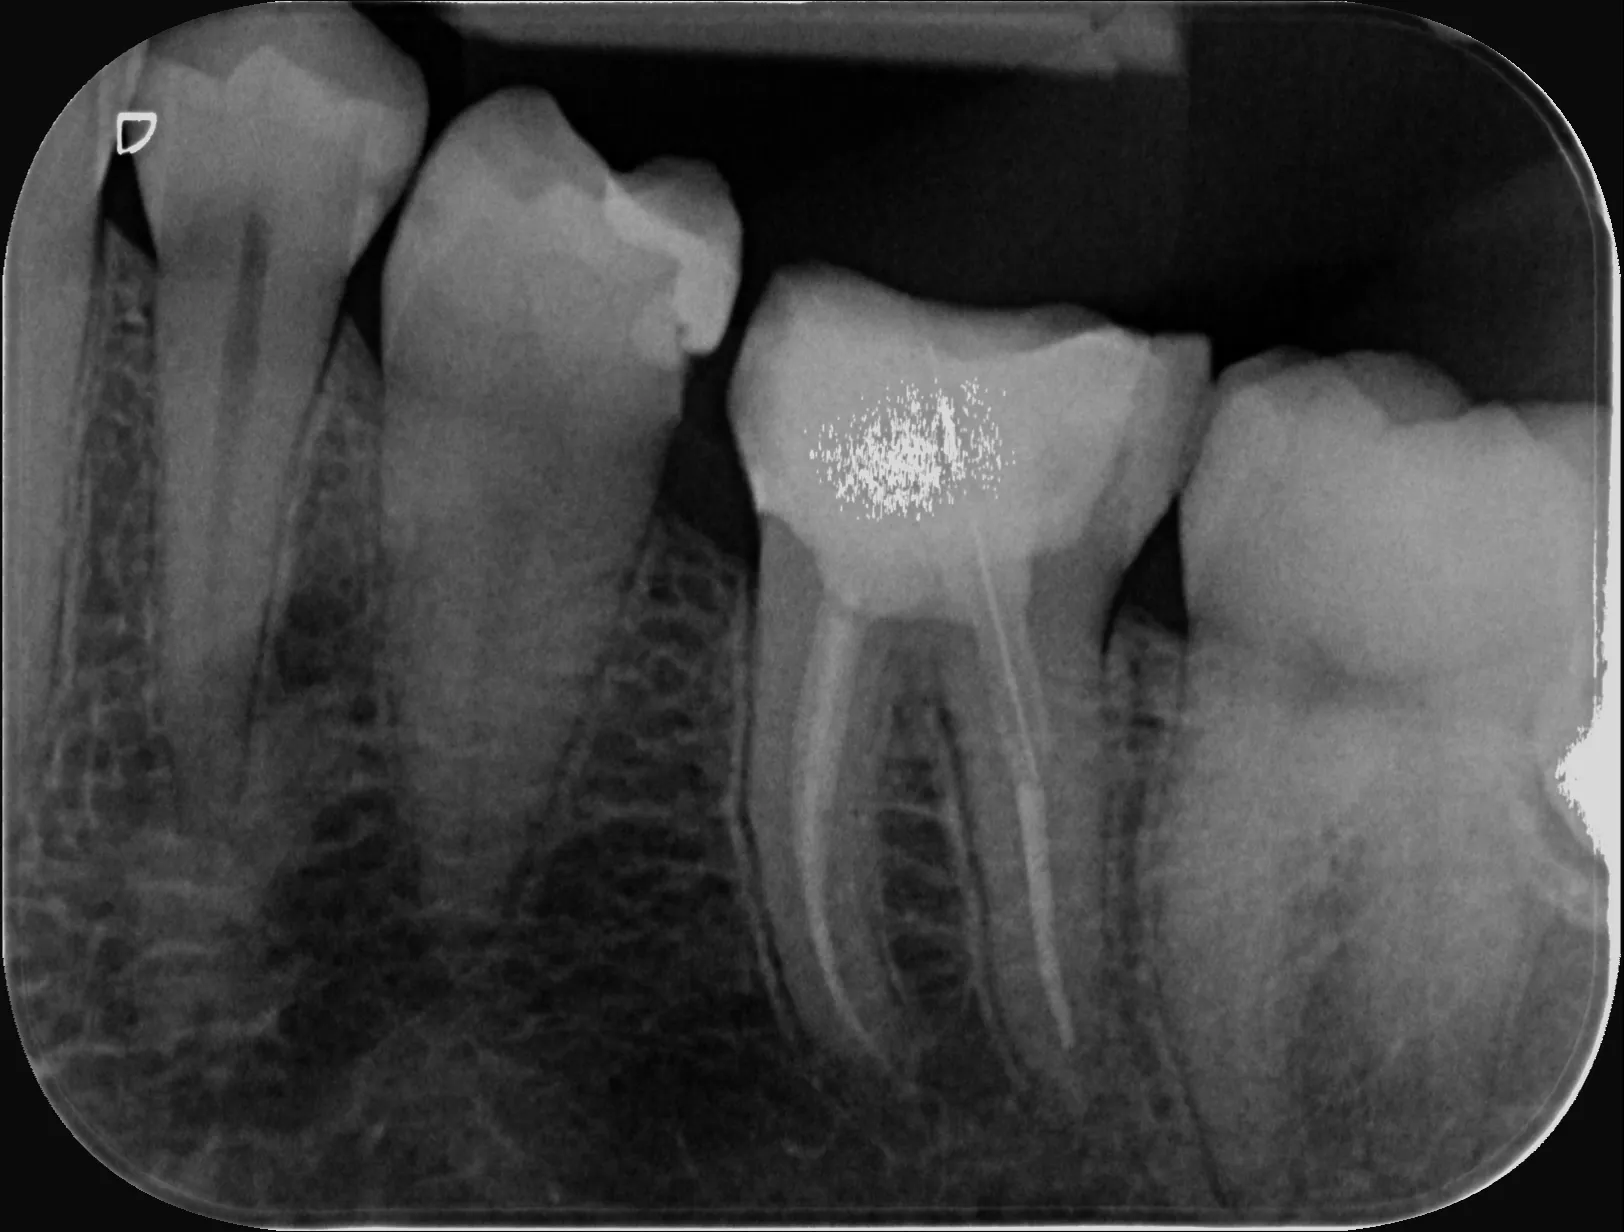

1 – Radiografie inițială